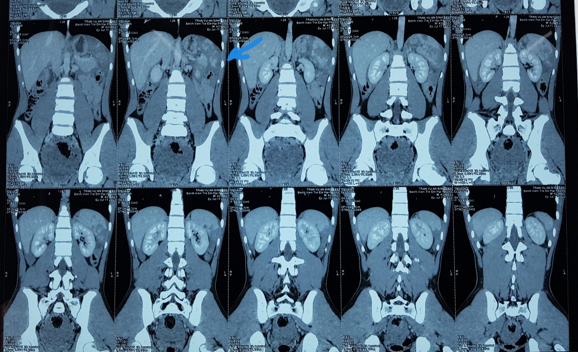

nghiệm máu, chụp CT ổ bụng, CT sọ não. Kết quả cho thấy CT ổ bụng có hình ảnh vỡ

lách độ IV, lách bị vỡ thành nhiều mảnh kèm theo có máu tụ quanh lách và nhiều

máu ở túi cùng Douglas (Hình 1).

Hình 1: Phim chụp CT ổ bụng có

hình ảnh vỡ lách độ IV, mũi tên chỉ vị trí vỡ lách.